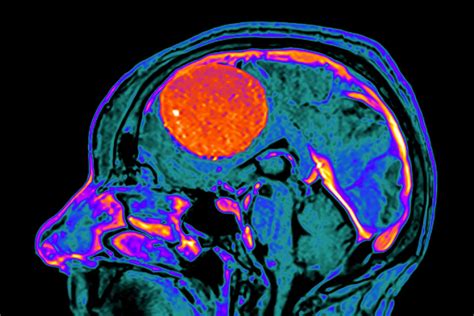

Receiving a diagnosis of a brain tumor can be an overwhelming experience, but understanding your options is the first step toward effective treatment. Among the various types of intracranial growths, a meningioma is one of the most common, accounting for approximately one-third of all primary brain tumors. While many meningiomas are benign and grow slowly, their location can exert pressure on critical brain structures, necessitating professional medical intervention. When a neurosurgeon determines that removal is the best path forward, Brain Tumor Meningioma Surgery becomes a vital procedure aimed at alleviating symptoms and preventing further neurological impairment.

• MRI (Magnetic Resonance Imaging): Provides highly detailed images of the tumor and its interaction with adjacent brain matter.